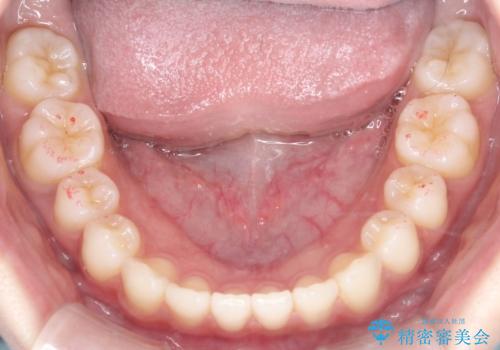

初診時の歯並びの状態としては、上下前歯が噛んでいない開口という状態であり、前歯を中心に上下とも歯の間に隙間がある状態でした。

抜歯は行わずマウスピース治療による主訴の改善を計画しました。

また、開口、スキッ歯の根本的な原因として考えられる、舌突出癖による後戻りの防止のためにMFTという舌のトレーニングも行いました。